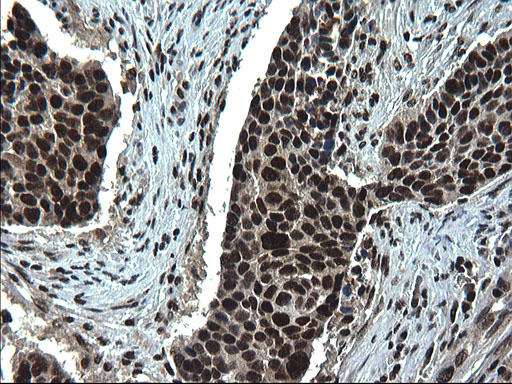

Preferentially expressed in a range of tumor tissues including colon, lung, liver, breast, prostate, stomach, uterine endometrium and cervical cancers with higher levels in tumors than in adjacent non-tumor tissue (at protein level).